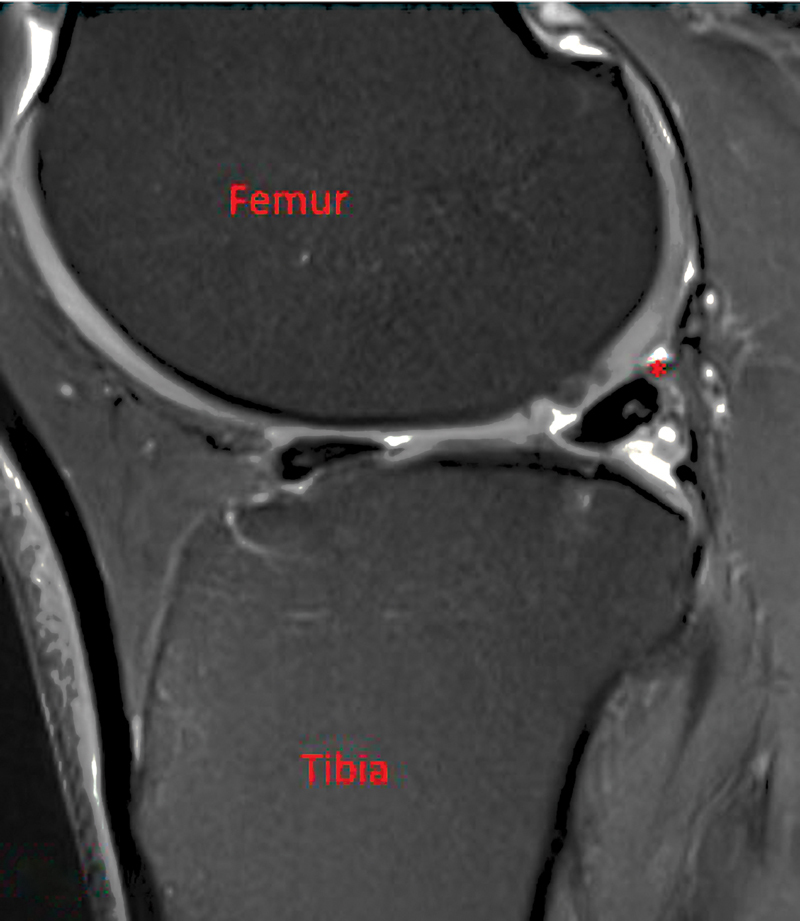

This case involves a healthy male with painful lateral knee pain and snapping after a hyperextension injury. Initially, this was felt to be from a displaced lateral meniscus tear; however, he failed to improve after meniscal debridement. Further workup with an ultrasound and magnetic resonance imaging identified an aberrant biceps femoris anatomy. He was taken to the operating room and the aberrant slip was identified. A tenodesis of the aberrant slip to the biceps femoris was completed. This resolved the patient's pain and snapping, and he was able to return to all activities.

Abstract Image